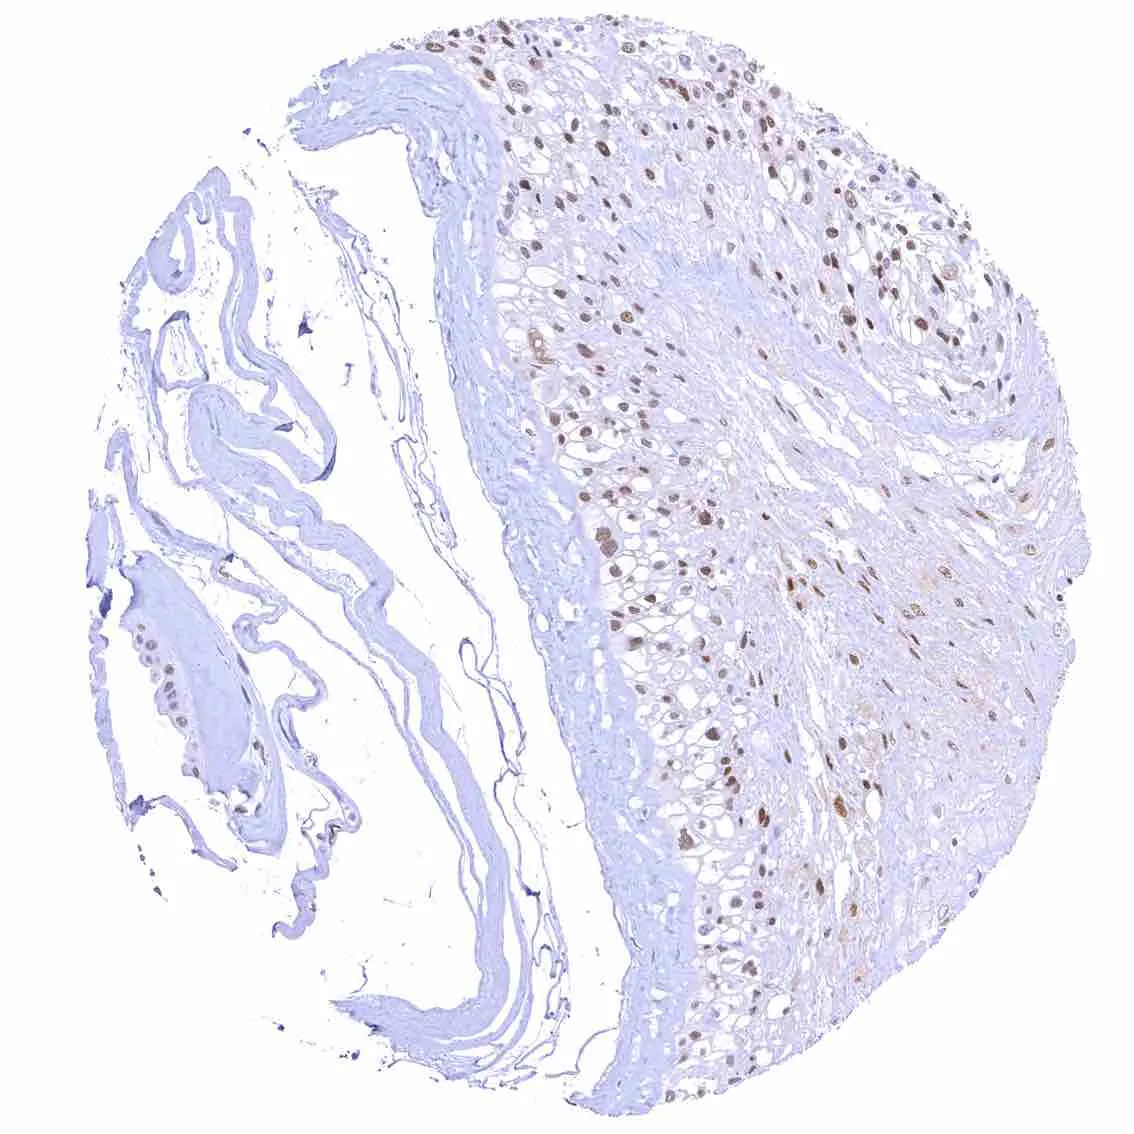

Skin – Moderate to strong nuclear p27 staining occurs in a large fraction of squamous epithelial cells and predominates in the more mature cell layers (top 50_ of the epidermis).

Skin, hairfollicel and sebaceous glands – Moderate to strong nuclear p27 staining in all cells of sebaceous glands.